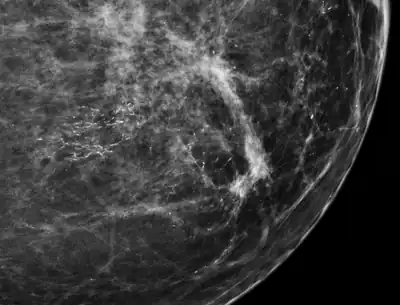

Mammogram microcalcifications in ductal carcinoma in situ

Microcalcifications are tiny deposits of calcium salts that are too small to be felt but can be detected by imaging.[1] They can be scattered throughout the mammary gland, or occur in clusters. Microcalcifications can be an early sign of breast cancer. Based on morphology, it is possible to classify by radiography how likely microcalcifications are to indicate cancer. [2]